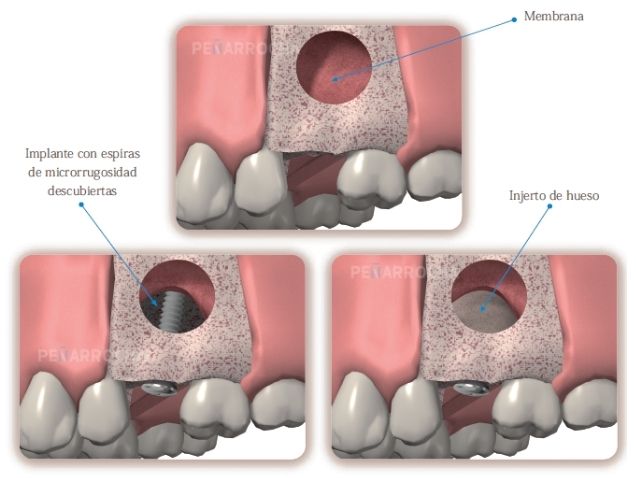

1. Elevación de seno por ventana lateral

Es la técnica más utilizada cuando hay menos de 5 mm de altura ósea disponible.

Proceso de elevación de seno maxilar por ventana lateral:

1. Se realiza una pequeña apertura en el lateral del hueso maxilar.

2. Se eleva la membrana sinusal con cuidado para no dañarla.

3. Se rellena el espacio con injerto óseo, que puede ser autólogo, de banco o sintético.

4. Se deja cicatrizar entre 4 y 9 meses antes de colocar los implantes.

Ventajas:

• Permite ganar una mayor cantidad de hueso.

• Ideal para casos de reabsorción ósea avanzada.

• Elevación directa de seno maxilar.